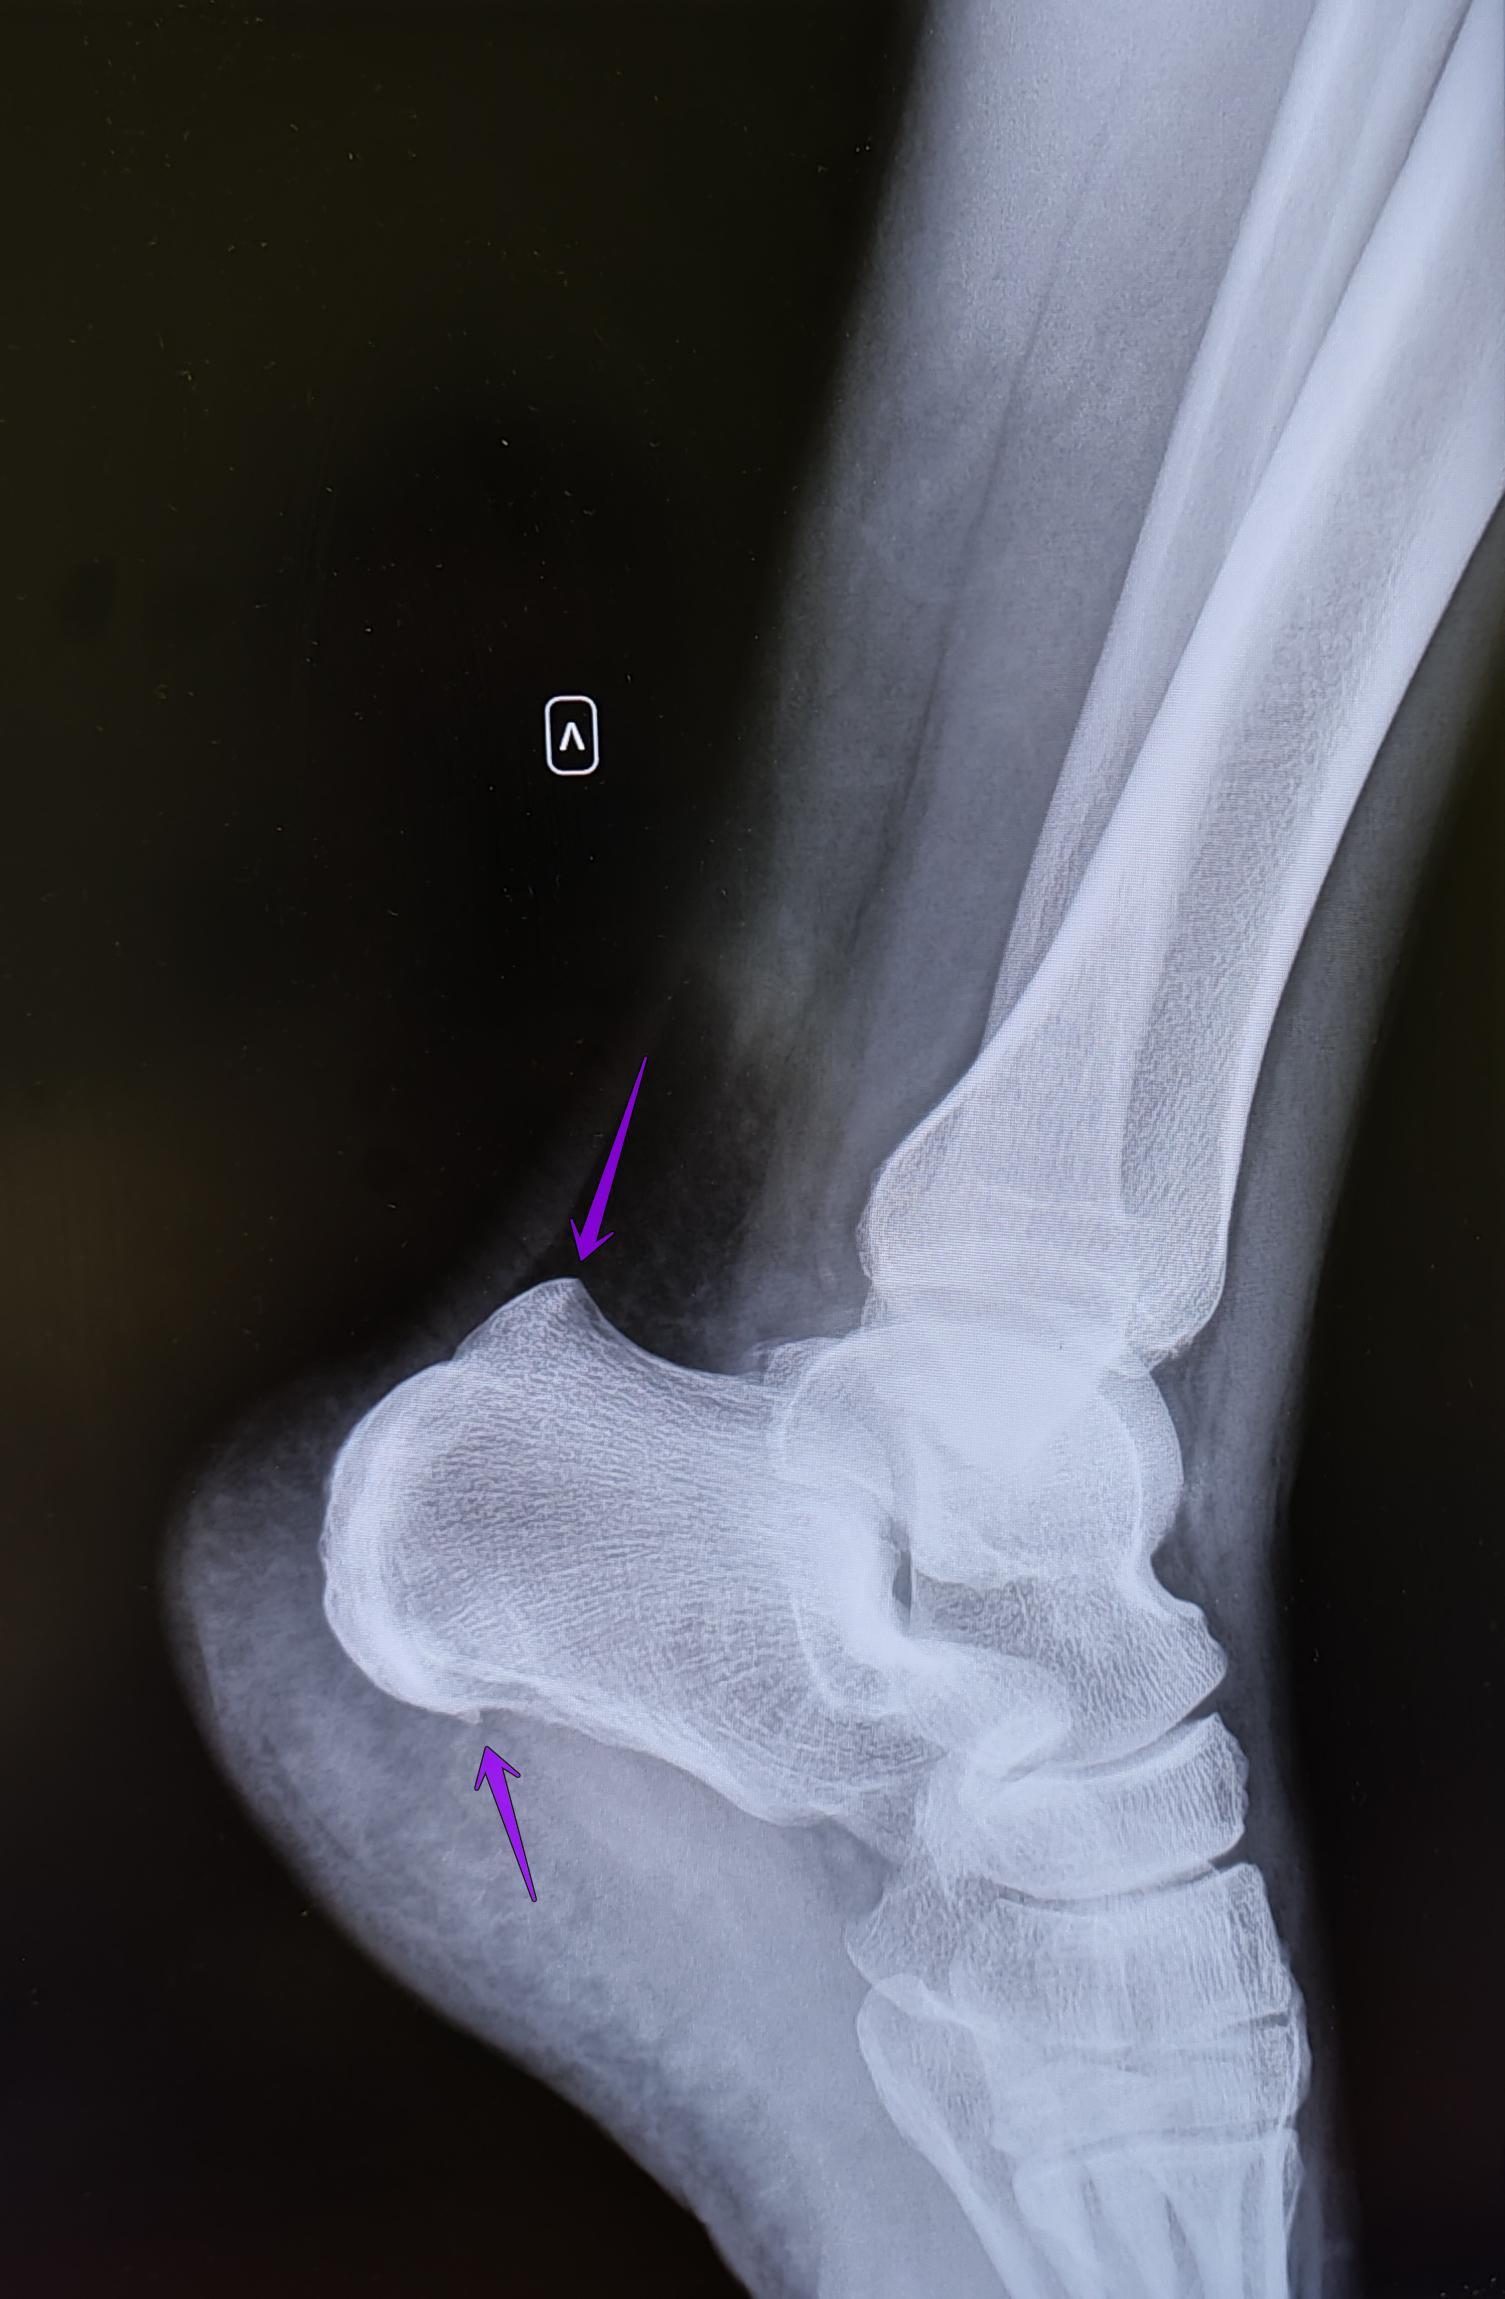

Описание: на Р-граммах правой и левой пяточных костей-травматических, деструктивных изменений не выявлено, структура костной ткани не изменена. В месте прикрепления подошвенных апоневрозов к буграм пяточных костей-визуализируются костные экзостозы. Верхняя часть бугров пяточных костей увеличена в размерах, имеет треугольную форму на широком основании. Заключение: Двусторонняя деформация Хаглунда. Двусторонние пяточные "шпоры".

При отсутствии длительного анамнеза воспалительного процесса, частых обращений с болевым синдромом, стац. лечения по поводу болевого синдрома, решение выносится на основании ст.65(Хирургические болезни и поражения костей, крупных суставов, хрящей:) г, Б-3:призывник годен к военной службе с незначительными ограничениями.